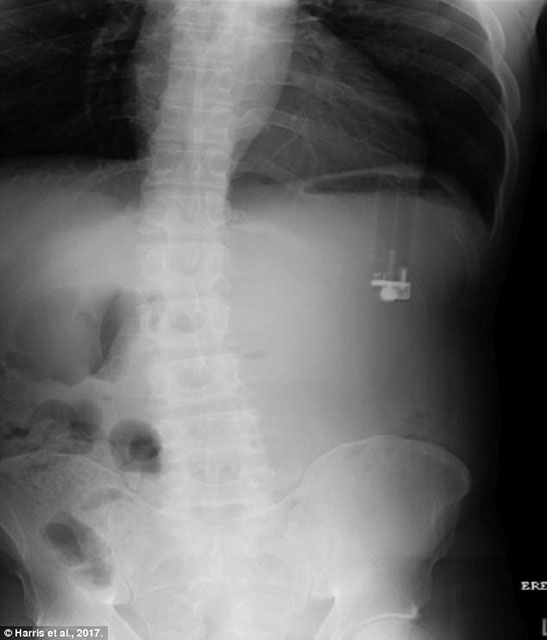

Bitmek bilmeyen kusma ve şiddetli karın ağrısıyla acile geldiğinde doktorları bile hayrete düşürdü.49 yaşındaki adamın çakmak yuttuğu anlaşılınca adam acilen ameliyata alındı.

Operasyon sırasında sızdıran çakmağın midesinde delik açtığı ortaya çıktı. Çakmağın içindeki sıvı, mide astarını mide asidinden ayıran mukusu delip geçmişti.

Case Reports in Emergency Medicine’de yazan doktorlar, bunun bu şekilde gerçekleşen ilk vaka olduğunu belirtti çünkü ilk kez çakmağın içindeki sıvı akmıştı. Başarılı bir operasyonla çakmak alınırken 2 ayın sonunda şizofreni hastası adamın midesi tamamen iyileşti.